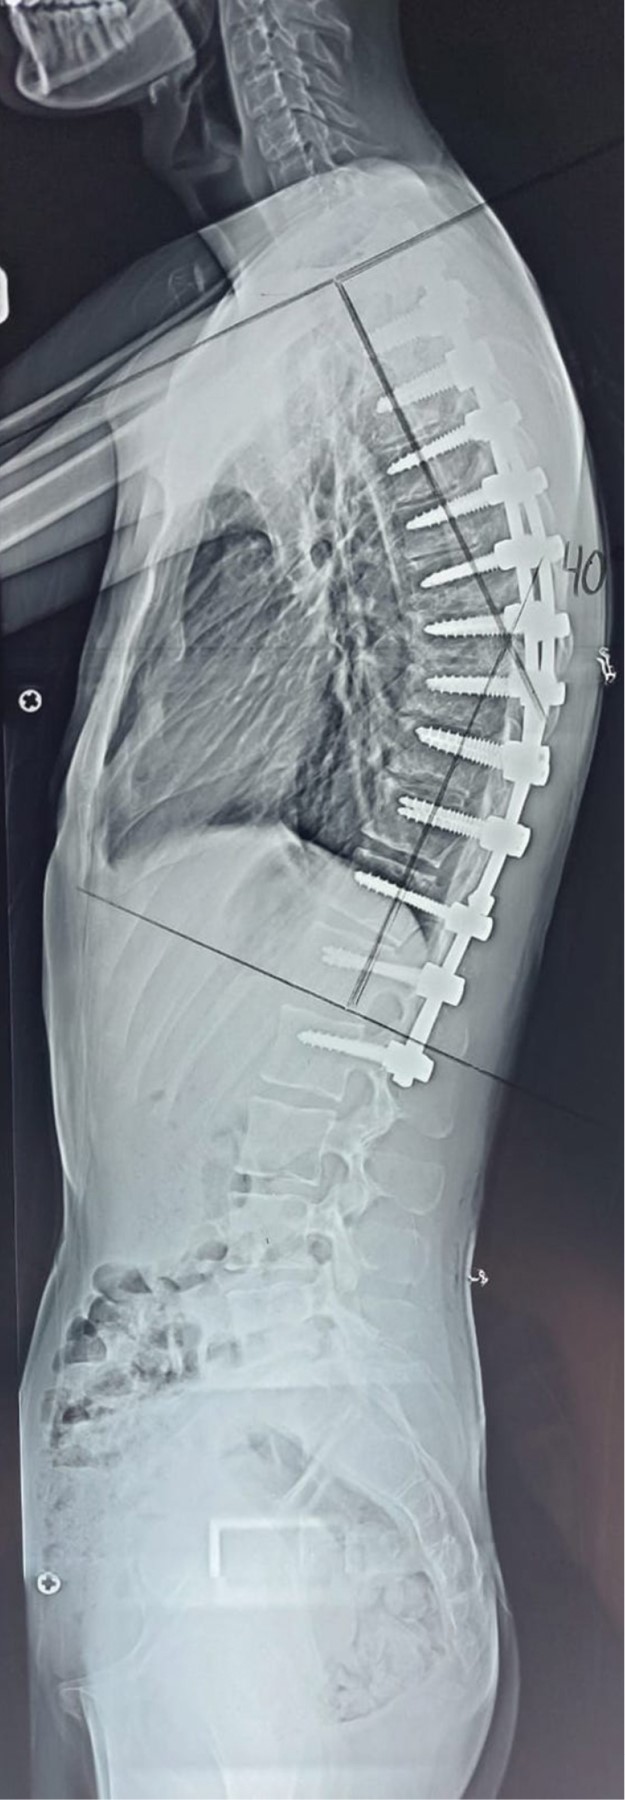

Paciente masculino de 22 años de edad y sin antecedentes de relevancia, el cual se presenta a consulta por deformidad, la cual le crea inseguridad estética y dolor recurrente de región torácica. Se solicitan radiografías anteroposterior (AP) y lateral panorámicas de columna, se detecta una deformidad de 105° de cifosis torácica (Figuras 1 y 2). Se propone al paciente realización de instrumentación posterior y fusión con corrección de curva torácica, quien acepta el tratamiento. Se realiza cirugía de instrumentación y fusión posterior exclusiva de T2 a L2 con tornillos poliaxiales mediante neuronavegación con O-ARM™ y neuromonitoreo (Figuras 3, 4 y 5). El paciente muestra buena evolución inmediata con una pérdida sanguínea menor de 200 ml durante las tres horas de procedimiento quirúrgico, además de buena evolución durante el primer, tercer y sexto mes con desaparición del dolor y corrección de curva a 40°(Figuras 6 y 7).

Las deformidades de columna son uno de los principales retos para los cirujanos especializados, ya que la anatomía se encuentra totalmente alterada perdiendo las referencias acostumbradas. La cirugía de alta tecnología mediante neuronavegación parece ser una excelente opción en deformidades, ya que facilita la colocación de tornillos pediculares, disminuye tiempos, pérdida sanguínea y produce precisión en la colocación de implantes. Sin duda alguna la tecnología está cambiando al mundo, esto incluye al ámbito médico y quirúrgico, lo que antes era un sueño, hoy puede ser realidad. Deberá evaluarse el costo-beneficio, a pesar de ello el uso de la neuronavegación se vuelve más accesible cada día y encamina a la cirugía mundial de columna a una nueva era donde las deformidades podrán ser tratadas con mejores resultados que los conocidos hasta ahora.